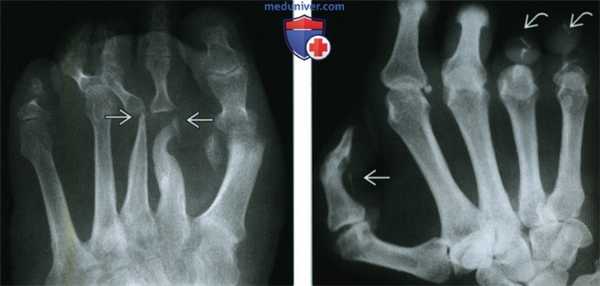

(Слева) Рентгенография в ПЗ проекции: визуализируются большие вдавления вдоль медиального и латерального краев средней трети стопы и обширное сращение костей в межплюсневых, плюсне-предплюсневых и межпредплюсневых суставах. Отмечаются остаточные дефекты, эрозии от вдавления.

(Слева) Рентгенография в ПЗ проекции, выполненная у пациента с лепрой: разрушение плюсневых костей выражено значительно больше, чем дистальных фаланг. Этот случай не соответствует другим причинам акроостеолизиса, делая лепру наиболее вероятным диагнозом, что и было доказано.

(Справа) Рентгенография в ЗП проекции: выраженный акроостеолизис, большая часть фаланг разрушена. Кроме того, отмечается линейная кальцификация в зоне нерва пальца. Эта комбинация признаков патогномонична для лепры.